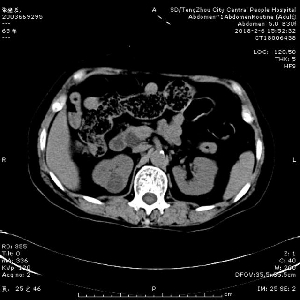

急診ERCP,讓生命垂危患者轉危為安

近日,消化內二科為一名急性梗阻化膿性膽管炎合并感染性休克患者進行急診ERCP(十二指腸鏡逆行性胰膽管造影術)手術治療,成功解除膽道梗阻,挽救了患者寶貴的生命,并讓患者在除夕夜和家人團聚,開心過上了春節。 2